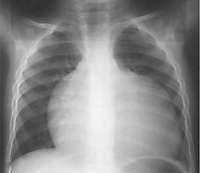

X radiation is special because it has a very high energy level that allows the x ray beam to penetrate through the body and create an image or picture.

Kid definition x ray. They are very useful because they can go through substances that light cannot. The passage of x rays through materials including biological tissue can be recorded. A doctor will decide when you need an x ray and what body part needs to be x rayed.

X rays have a shorter wavelength and therefore more energy than ultraviolet radiation. Dictionary and thesaurus definition of x ray notice. Like light x rays are a form of radiation.

These are all parts of the. Along with this x ray for kids article you can browse our other articles about imaging exams for children like mri or ct you can read through this information yourself or read it to your child. X radiation is a kind of electromagnetic radiation.